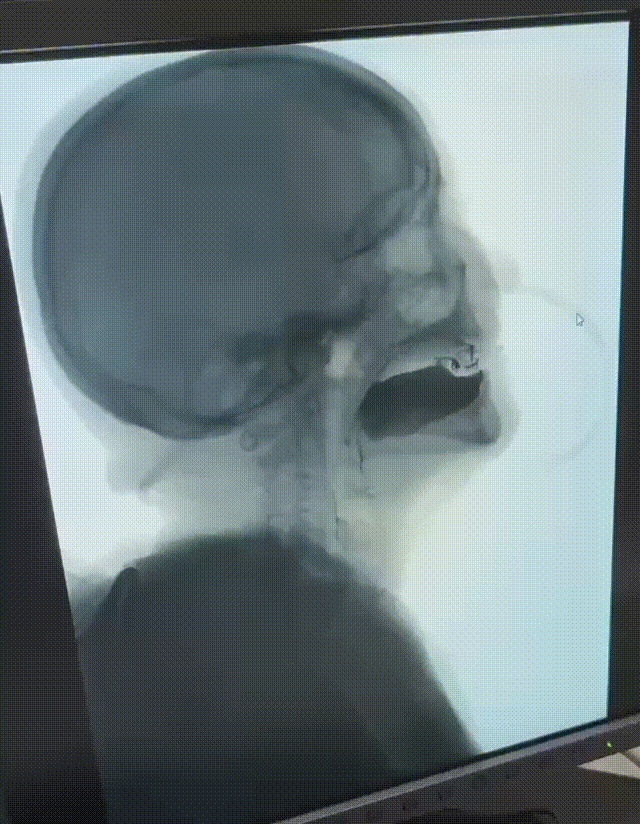

吞咽造影检查是指在X线透视下,对吞咽过程中的口、咽、喉、食管的吞咽运动进行特殊造影。医生通过侧位及正位成像,观察患者吞咽不同黏稠度、不同剂量的造影剂,进一步评估出四个吞咽阶段(包括口腔准备期、口腔期、咽期、食管期)的异常情况。

吞咽造影检查可以明确吞咽障碍的存在和类型;确定吞咽障碍的部位、受损程度和代偿情况;分析吞咽障碍的时期,指导安全进食;判断误吸及其严重程度,对肺炎的预防有重要作用,因此被认为是最全面、可靠的吞咽功能检查方法之一。